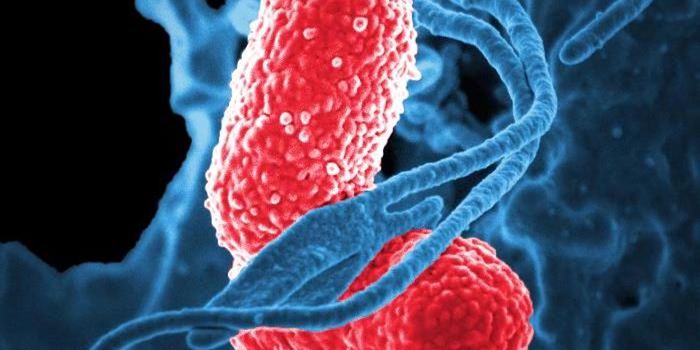

MAR 09, 2022MicrobiologyAntibiotic resistance is already a major threat to public health; in 2019 alone, antibiotic resistant bacterial infectio ...

JAN 22, 2022MicrobiologyAntibiotic-resistant infections pose a serious threat to human health, which is expected to get worse. Bacterial infecti ...

APR 05, 2021MicrobiologyMany types of bacteria often live harmlessly in and on animals and humans, but some bacteria pose a threat. Salmonella b ...